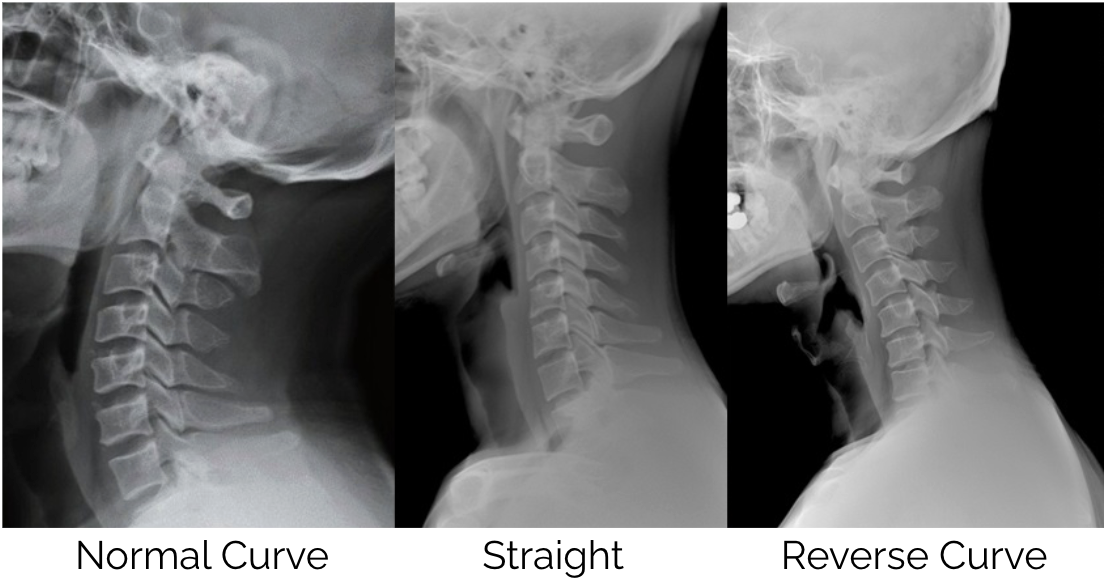

Most of us spend hours each day looking at screens — laptops at work, phones between tasks, tablets in the evening. It has become so normal that we rarely stop to think about what that sustained position is doing to our bodies. But researchers and clinicians have increasingly drawn attention to a pattern of postural change now commonly referred to as "tech neck" — and the effects go well beyond a sore neck at the end of the day.

As the technology in our lives continues to advance, most of us find ourselves spending more and more time sitting and for longer periods. Our desk jobs, study and even our increasing amounts of time on screens (phones, tablets and TV) over the past 10-20 years are now having a significant effect on our overall health and wellbeing because we are becoming more sedentary and not moving our bodies enough on a daily basis.